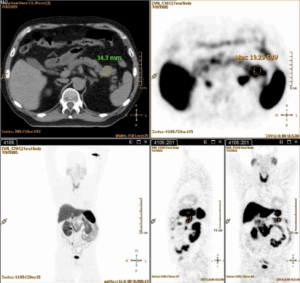

A staging PET-DOTANOC was done and showed uptake in the pancreatic tail lesion (SUV max 19,3) and in some peri-centimetric paraaortic lymph nodes (SUV max 6,3) (Fig. 4).

Fig. 4. PET-DOTANOC: Uptake in the pancreatic tail.